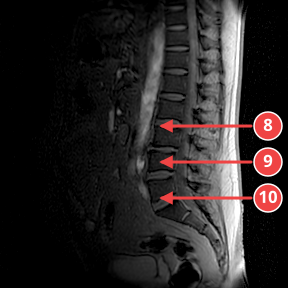

IMG-0001-00005.dcmSURVEY

Обзорная коронарная проекция. Визуализируются признаки дегенеративных изменений межпозвонковых дисков на нескольких уровнях поясничного отдела.

Аномалии

- [6] Дегенерация диска L4-L5 с протрузией — medium — Сужение межпозвонкового пространства, снижение сигнала, протрузия. уверенность 75%